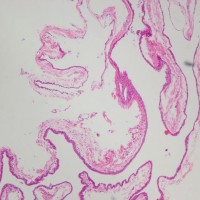

前頭側頭開頭 pterional approachで全摘出しました。発生母地は下垂体柄前面でしたが完全摘出しました。術後に下垂体機能は正常に保たれています。病理所見は一層の上皮細胞でのう胞壁が構成されることが特徴です。これをラトケのう胞と呼ぶかどうか議論のあるところで,おそらく正確には内胚葉のう胞 endodermal cystと診断します。